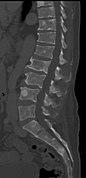

Medical imaging

The diagnostic examination of a person with suspected multiple myeloma typically includes a skeletal survey. This is a series of X-rays of the skull, axial skeleton, and proximal long bones. Myeloma activity sometimes appears as "lytic lesions" (with local disappearance of normal bone due to resorption). And on the skull X-ray as "punched-out lesions" (pepper-pot skull). Lesions may also be sclerotic, which is seen as radiodense.[52] Overall, the radiodensity of myeloma is between −30 and 120 Hounsfield units (HU).[53] Magnetic resonance imaging is more sensitive than simple X-rays in the detection of lytic lesions, and may supersede a skeletal survey, especially when vertebral disease is suspected. Occasionally, a CT scan is performed to measure the size of soft-tissue plasmacytomas. Bone scans are typically not of any additional value in the workup of people with myeloma (no new bone formation; lytic lesions not well visualized on bone scan).